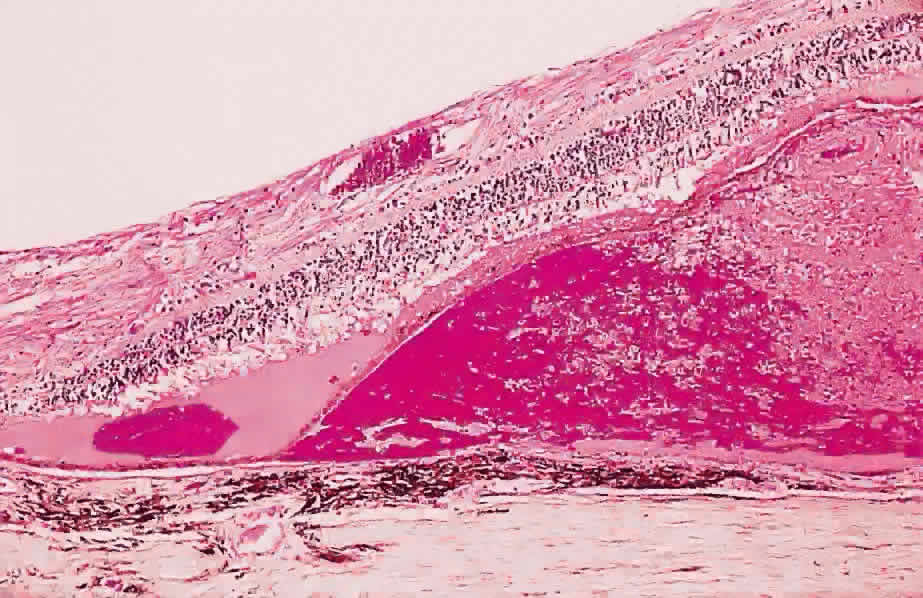

Fig. 12. Section of the eye showing subretinal hemorrhage. (Courtesy of Ralph C. Eagle Jr, MD, Philadelphia, PA) Fig. 12. Section of the eye showing subretinal hemorrhage. (Courtesy of Ralph C. Eagle Jr, MD, Philadelphia, PA)